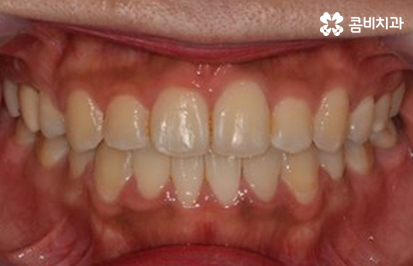

장치를 풀어내고 유지 관리가 시작된 모습

비교적 빨리 진료를 끝낼 수 있는 클리피씨교정 마저도

장기적인 관점에서 바라볼 수 밖에 없습니다.